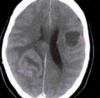

Mujer de más de 40 años que presenta un dolor muy intenso al realizar ejercicio o esfuerzo y cursa con bajo nivel de consciencia

A

Hemorragia subaracnoidea ( ACA )

Etiologia ictus hemorragico intraparenquimatoso

HTA ( ganglios basales ) profundo Malf AV / Aneurismas Angiopatia amiloide ( lobar ) multiples i recurrentes en personas mayores

Etiologia ictus hemorragico subaracnoideo

TCE Aneurismas saculares ( triada: cefalea en trueno, rigidez de nuca, valsalva ( vomitos nauseas )